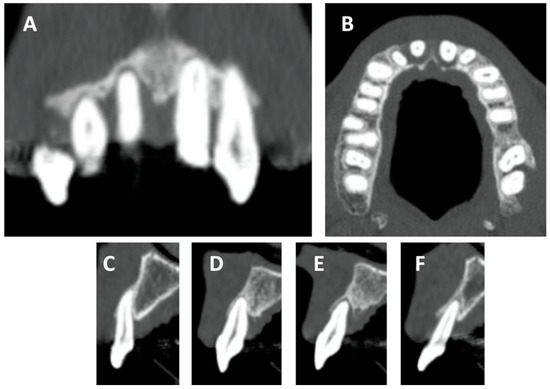

Hyperbaric Oxygen Therapy and A-PRF Pre-Treated Implants in Severe Periodontitis: A Case Report

2. Case Report